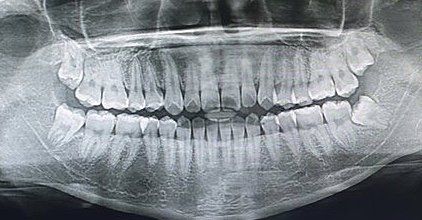

지금 나이는 만 19세이고 어렸을 때 뺄 수록 좋다고 들었습니다. 아래 사랑니는 둘다 얼마전에 뽑았고 윗사랑니는 두개 다 조금씩 나오고 있는 중입니다. 윗사랑니도 빼야하나요? 아래 사랑니 날때처럼 아프진 않습니다. 빼야한다면 당장 빼야하는지 아니면 조금 더 나왔을 때 빼는게 좋은지도 알려주세요!

파라노마 사진만으로는 정확히 사랑니 상태를 확인할 수 없어 정확한 답은 불가한 점 양해 부탁드립니다.

사진으로만 봤을 땐 윗 사랑니는 좀더 나온다음에 빼주는게 좋겠습니다.